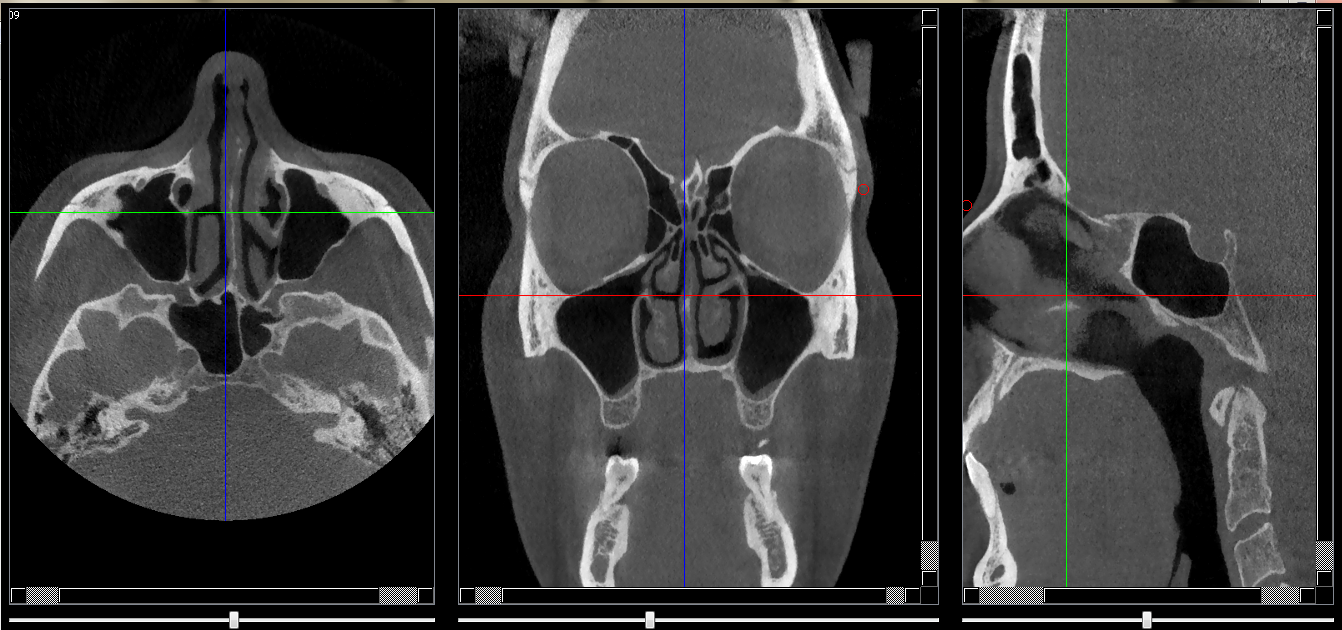

Structures osseuses

Septum nasal

Repères anatomiques

- Coupe transversale

- Début : Palais dur

- Fin : Crista galli

- Coupe frontale

- Début : Cornet nasal inf

- Fin : Fissure orbitaire sup

- Coupe saggitale

- Début : Cornet nasal droit

- Fin : Cornet nasal gauche